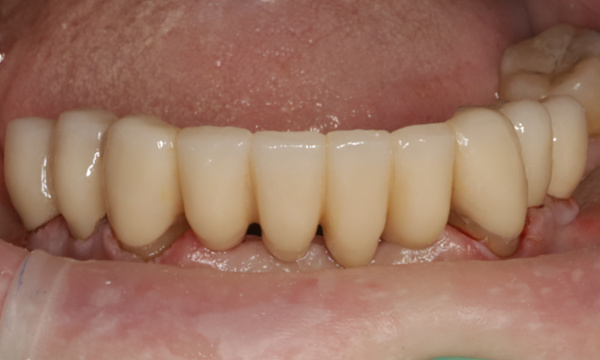

Zirconia Bridge from lower canine to canine

We elected to provide a bridge which held on to her canines on either side, and remove (extract) the incisors and replace them with the bridge. We also placed zirconia crowns on her premolars.